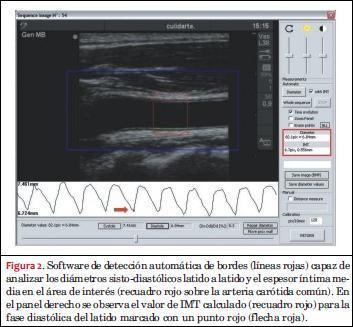

Onda del diámetro del pulso carotídeo y espesor íntima-media

Una vez obtenida la secuencia de imágenes del video se realizó el análisis mediante un equipo de procesamiento específico (Hemodyn 4M, Dinap SRL, Buenos Aires, Argentina). A partir de la aplicación del software a la secuencia de imágenes obtenida, se eligió una región de interés en un corte longitudinal de la arteria carótida común (a 1 cm del bulbo carotídeo) y se detectaron de manera automática los bordes de las paredes arteriales a partir de cambios en la impedancia acústica (Z) de los materiales, obteniendo para cada video la morfología del diámetro del pulso arterial latido a latido (con sus valores sisto-diastólicos) y el IMT de la pared posterior en el fin de la diástole (figuras 2 y 3A).